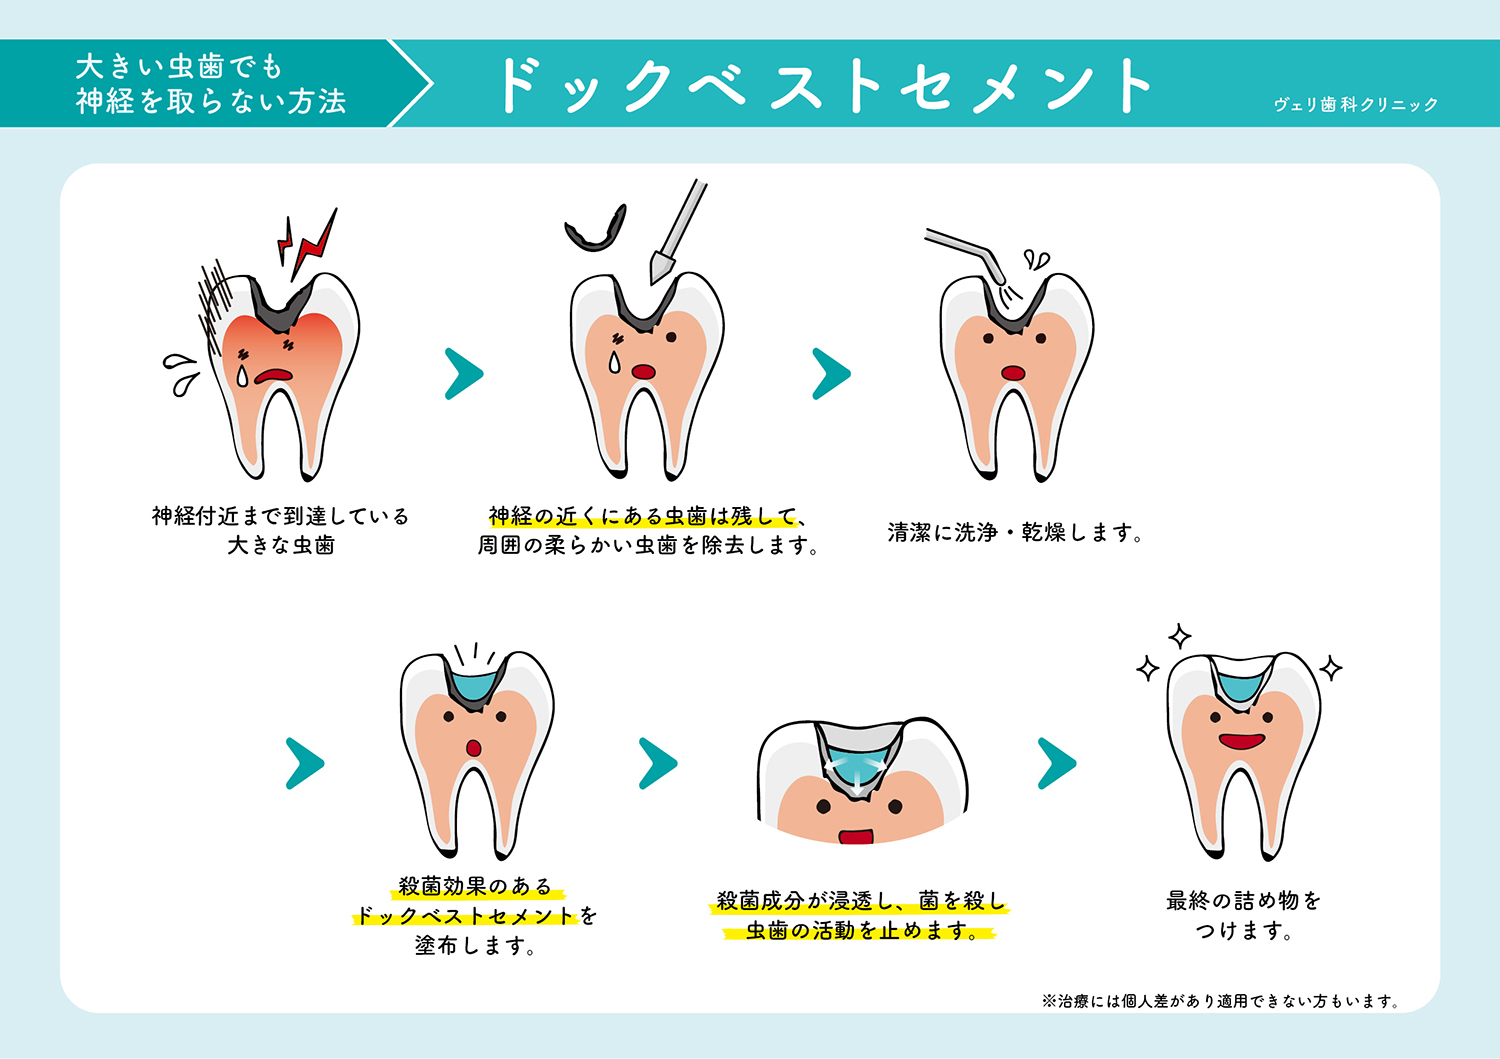

虫歯でお困りの方へ ヴェリ歯科クリニック